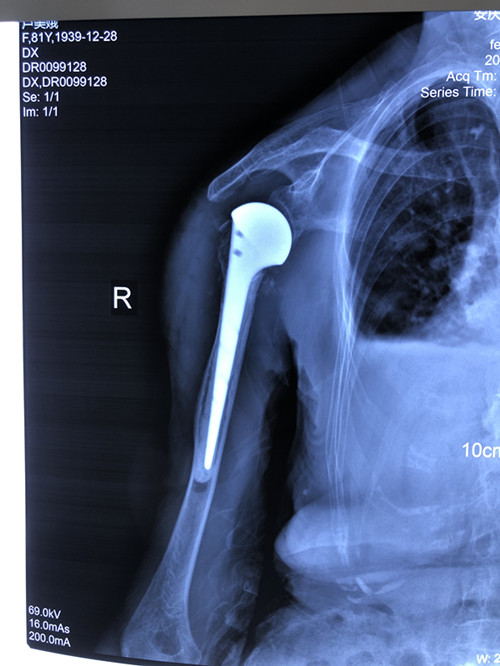

人工肱骨頭置換術(shù)是一個“精細活”,技術(shù)要求高、操作難度大,人工假體尺寸的選擇、安放的位置都很有講究。手術(shù)當天,張明龍主任帶領(lǐng)團隊僅用時一個多小時,就成功將“人工肩關(guān)節(jié)”植入患者體內(nèi)。

術(shù)后,李老太恢復良好,第3天就開始進行輕度被動前屈、外展活動,一周后恢復擺動、康復功能鍛煉。

攻堅克難、不斷創(chuàng)新。此次是石化醫(yī)院骨科團隊首次獨立完成人工肱骨頭置換術(shù),填補了醫(yī)院該項技術(shù)的空白,也標志著科室治療水平又邁上了一個新的臺階。